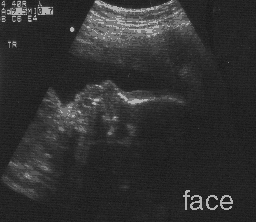

Ultrasound showing Benjamin's face